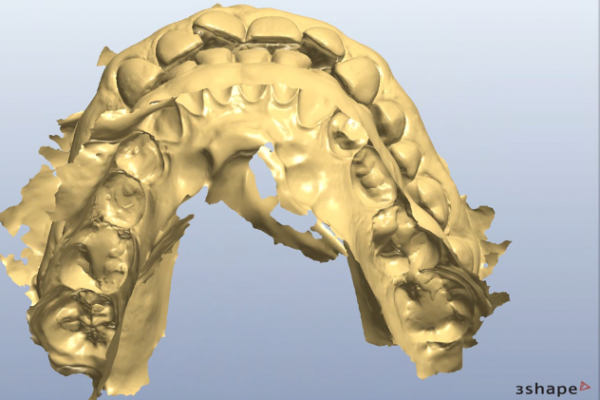

So, prior to a hygiene work up, the patient was then assessed from an orthodontic perspective for short-term pre-restorative orthodontics. This was to improve tooth position (Figures 2 a,b and c) and allow for a less destructive tooth preparation.